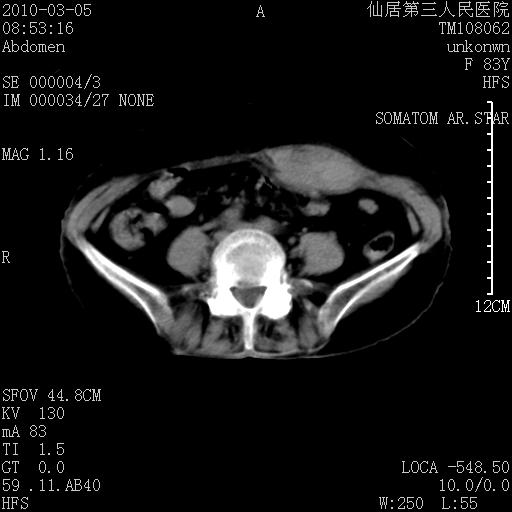

标题: CT24879:腹直肌病变。在线等。

女性,83y,腹痛一周。

考虑左侧腹直肌血肿,肿瘤性病变待排。

增强看看,mfh可能性大,次之可考虑血肿、bfh、转移瘤、神经纤维瘤、侵袭性韧带样纤维瘤等。肝内钙化灶,右肾结石。

血肿,纤维瘤,子宫内膜异位都有可能。